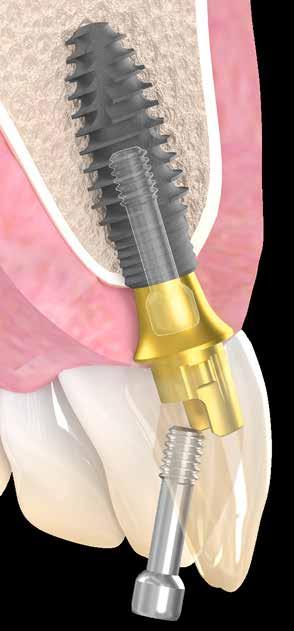

Az implantátumok behelyezése az elülső és a hátsó régióba

Először a két elülső implantátumot (V3B+, MIS implantátumok) helyeztük be. Kúp alakú kapcsolatuk biztosítaná a biztos illeszkedést az abutment és az implantátum között, és minimalizálná a mikromozgásokat.

Minden implantátumot átlagosan 4-5 mm távolságra helyeztünk be a leendő ínyszéltől (5. a és 5. b ábra). Az optimális lágyszövetkezelést úgy értük el, hogy a gyógyuló felépítményeket a gyógyult gerincekre helyeztük. Az azonnali

6. b kép: ...és a személyre szabott gyógyító felépítmény azonnali behelyezése.

implantátumokon is személyre szabott gyógyuló felépítményeket alkalmaztunk az ínyprofil megtartása érdekében (6. a–6. c ábra).